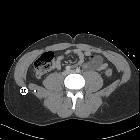

lumborum muscle • CT abdomen/pelvis (lower) axial - labeling questions - Ganzer Fall bei Radiopaedia

The muscle is a thick, irregular, quadrilateral-shaped muscle sheet that lies in the posterior abdominal wall on each side of the lumbar vertebrae. It is superficial to the psoas major muscle.